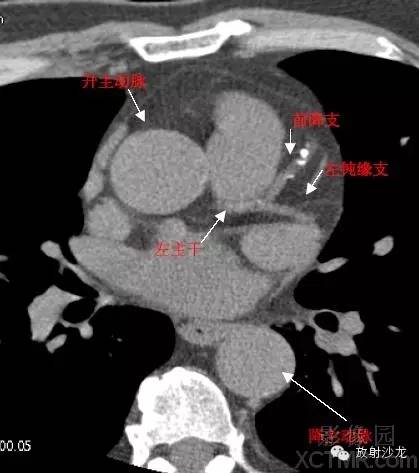

A.Aorta-Ascending Aorta升主动脉

D. Aorta-Descending Aorta降主动脉

LMA -Left Main Artery冠状动脉左主干

LAD -Left Anterior Descending Artery左前降支

LMB -Left Obtuse Marginal Branch 左边缘支(钝缘支)

RCA -Right Coronary Artery 右冠状动脉